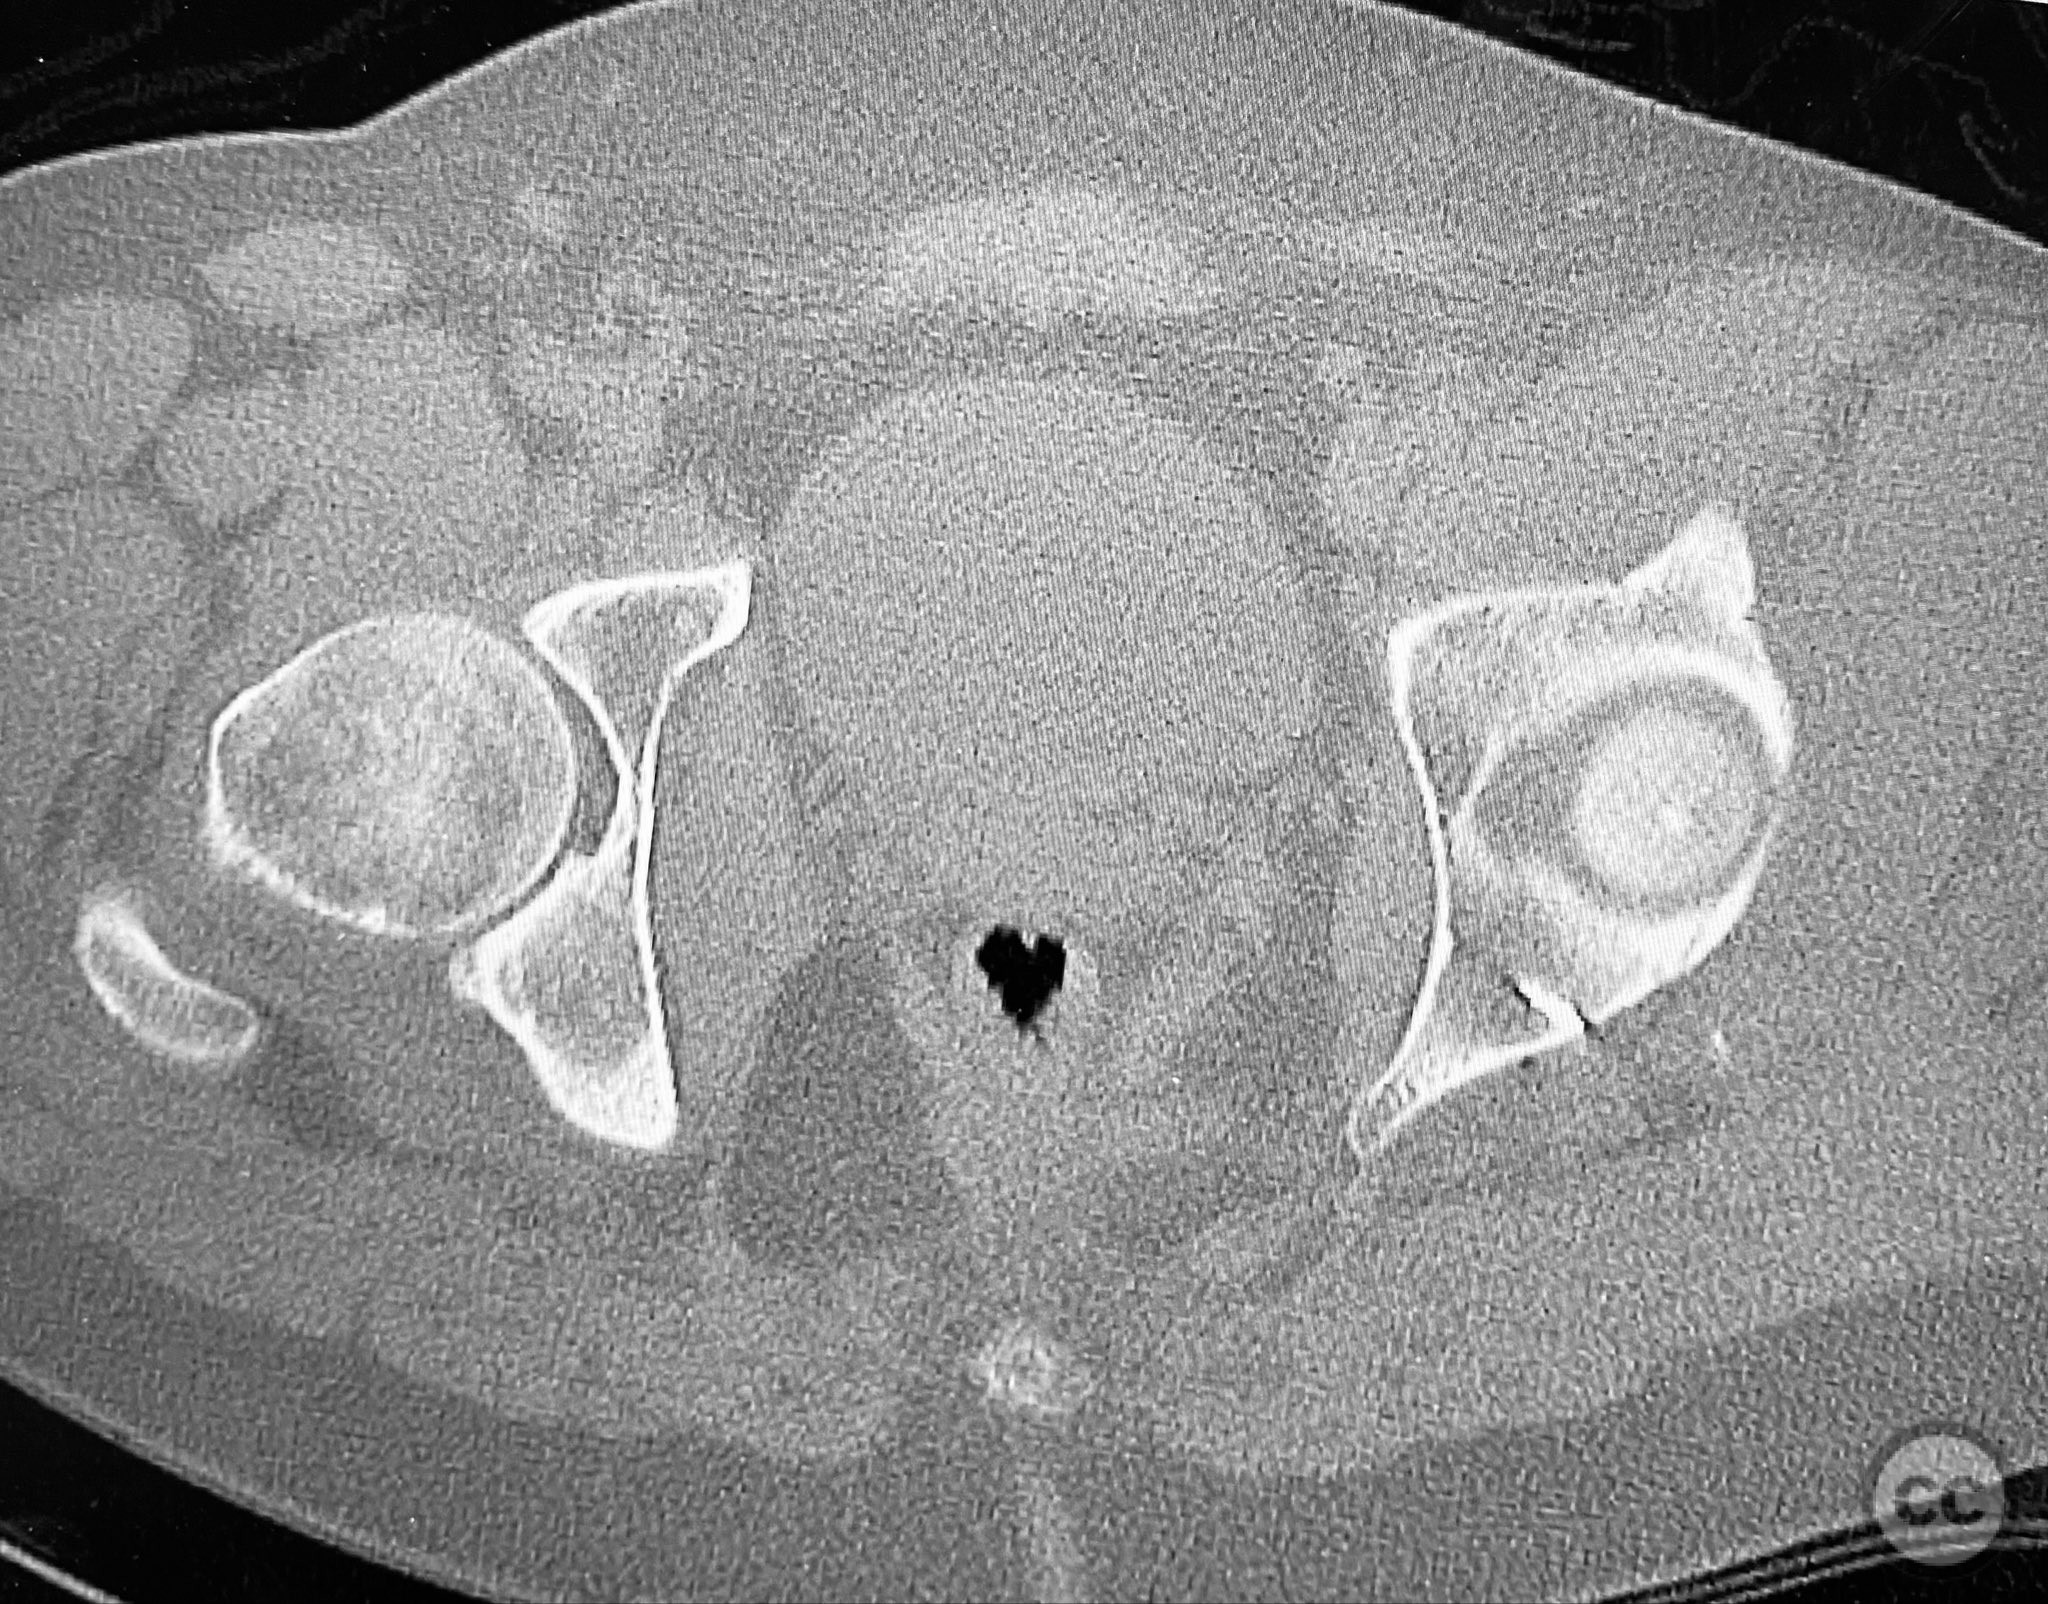

Posterior Wall Acetabular Fracture with Incarcerated Chondral Fragment and Hip Joint Asymmetry

Clinical and radiological findings:  A patient involved in a motor vehicle collision presented with left hip pain exacerbated by any attempted movement. Initial axial and surface-rendered computed tomography (CT) imaging demonstrated an essentially nondisplaced posterior wall (PW) acetabular fracture (AO/OTA 62-A1.1). However, the anteroposterior (AP) scan image and coronal reconstructions revealed significant hip joint asymmetry. Examination under anesthesia with fluoroscopic guidance confirmed persistent joint incongruity, with the femoral head subluxating posteriorly at 50–60 degrees of flexion. A pure chondral fragment was identified as being interposed between the femoral head and the intact region of the posterior wall, accounting for the clinical and radiological asymmetry.